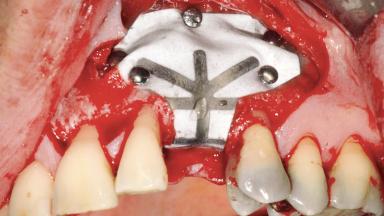

Guided Bone Regeneration (GBR) with a Particulated Autologous Graft and a ePTFE-Reinforced Membrane for Vertical Augmentation of a Single-Tooth Edentulous Space in the Esthetic Zone

Bone Augmentation Staged|Vertical

Augmentation Materials Autogenous chips|Membrane

Bone Volume Deficient vertically or deficient vertically AND horizontally